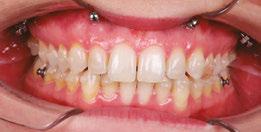

Stan was referred to my office by a TMD specialist. His chief complaints were he could not chew or open his mouth without pain. It seemed the less he chewed, the more pain he experienced. As a result, an Orofacial Myofunctional Therapy (OMT) program was created to help support his muscles of the TMJ and craniofacial respiratory complex. He used his splint as instructed by his specialist. However, his anterior open bite widened, and his teeth became more misaligned over time.

Upon closer examination, there were contributing factors that led to his discomfort. Stan had been a stomach/face sleeper for years. He also bit his nails since childhood, had a smoking habit from his youth, and he was prone to ear infections. He had moderate tongue and buccal ties, obligate mouth breathing, aggravated by a deviated septum, narrow nares, low tongue resting posture, an anterior open bite, a lower jaw that deviated upon opening, and bouts of acid reflux.

When the tongue rests in the palate, it impacts facial development especially for children who are still growing. An adult, for example, like our friend Stan, the progress made is gradual but more likely to last a lifetime. Generally, therapy starts out once a week for about 2-3 months. Then therapy progresses to every other week for 2-3 months, and then changes to once a month for about 5 months for the rest of the year. The exercises are done a minimum of 2 times everyday. These exercises are designed to strengthen and tone the orofacial muscles, building brand new neuromuscular function. When the muscles of the face are well developed, it may favorably impact appearance and the overall integrity of the facial structures. The muscles of the face also include the tongue, lips, cheeks and neck. Although the therapy program is typically only a year, Stan really liked how good he felt and decided to continue with some of the exercises to this day. From the photos you can see how much the program has impacted his health and well-being.

During his therapy, there was a discussion about the possible benefits he may receive from having his jaws expanded, making more room for his tongue, then to be followed by a tongue and buccal frenums release. His intermolar width is 34 mm, and his intercanine width is 25 mm. I feel any expansion has a potential benefit.

Figure 4: 7 years later on April 10, 2024. Anterior open bite closed a bit

Figure 2: Initial assessment on December 15, 2016 (top left). Later September 20, 2017, his anterior openbite widened (top right)